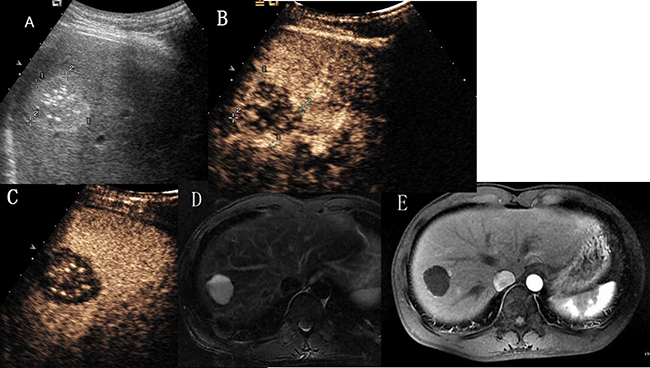

Figure 4: Hepatic hemangioma with no enhancement in all vascular phases. (A) Ultrasound revealed a hyperechoic mass with multiple spotty calcifications in hepatic segment VII. (B) and (C) CEUS showed none enhancement throughout the whole vascular period. (D) T2- weighted MR images revealed a high signal intensity lesion with fluid–fluid level. (E) Enhanced magnetic resonance showed no contrast enhanced in arterial phase.

Hepatic hemangiomas are being detected more frequently than before because of widespread application of routine ultrasound screening. Pathologically, hemangiomas are composed of many endothelium-lined vascular spaces separated by fibrous septa, and the collective size of their constituent vascular spaces may vary [9]. The differentiation of hemangiomas from other hepatic tumors is of great importance. CEUS has markedly improved the accurate diagnosis of hepatic hemangiomas, which is now possible in about 95% of cases [10]. It can provide diagnosis of hemangioma in most cases without requiring further investitation [11]. However, when the enhanced pattern was atypical, it may cause some uncertainty. Familiarity with the atypical appearance of hepatic hemangiomas on US and CEUS will increase the rate of correct primary diagnosis before surgery and histologic examination. In the present study, 11 hemangiomas showed washout in the delayed or portal phase, a common characteristic of them described in this series was their peripheral location on grayscale ultrasound, in one case near Glisson’s capsule. Hemangiomas showed hypoenhanced compared to the adjacent liver parenchyma in the delayed phase, just like subtypes (i), were reported by several authors [12, 13, 14]. The mechanisms of washout had several hypotheses, most researchers [12, 13] believed that this probably occurred because of microbubble rupture due to prolonged insonation, which was not adequately compensated because of progressive hemodilution of contrast agent and a slow blood flow in these lesions. Most hemangiomas showed washout in the delayed phase were located in the liver sub-capsule, and some near Glisson’s capsule [12, 14], we had the same situation in the study presented. Giannetti A et al. thought that hemangioms with arteriovenous and arteriosinusoidal shunts may washout in the early portal phase, which may have caused rapid elimination of contrast agent [14]. Hemangiomas with washout in the delayed or portal phase need differentiation from malignant liver tumors, especially metastasis. Bhayana et al. believed that the differential diagnosis between these lesions and metastases should be based on the time required for the elimination of microbubbles, which occurs much more rapidly in metastases [13]. During these 11 hemangiomas, 7 cases underwent contrast-enhanced magnetic resonance (CEMR), washout was not seen in all the cases. Magnetic resonance (MR) contrast agents had an extravascular equilibrium phase, and the interstitial portion of the hemangioma was filled during the delayed phase of the examination, which resulting in a hyper-isointense appearance compared with the adjacent parenchyma [15]. In our experience, hemangiomas with atypical appearance on CEUS due to washout may be diagnosed on the peripheral nodular enhancement and progression of centripedal filling in the arterial and portal phases of the examination. Besides washout in the late phase, the next most common atypical appearance of hepatic hemangiomas on CEUS was just peripheral enhancement without the progress of fill-in in all the vascular phases, just like subtypes (ii) and subtypes (iii). Since thrombo-haemorrhagic episodes, cystic degeneration, fibrosis or hyalinisation and calcium deposit may occur. Peripheral nodular enhancement was the typical feature of hemangioma in the arterial phase, if the peripheral nodular sustained hyper-isoechoic, it was helpful to make the diagnosis of hepatic hemangiomas. However, peripheral circular enhancement may cause some uncertainty, for it can be seen in other benign and malignant hepatic tumors, such as metastasis and inflammation. Without contrast enhancement throughout the whole enhancement period, just like subtypes (iv), is a very rare appearance of hemangioma, K. Mitsudo [16] reported a case of liver cavernous hemangioma which had multiple spotty calcifications arranged like a wreath and showed no enhancement on contrast-enhanced tomography. They misdiagnosed it as an old pyogenic abscess or cystadenoma preoperatively. Case 19 in our study was a 32-year-old man, he had a hyperechoic mass measuring 3.5 cm*3.1 cm in hepatic segment VII, which had multiple spotty calcifications and clear margin. Both CEUS and CEMR showed no contrast enhanced, on T2 weighted MR imaging, high signal intensity with fluid–fluid level could be seen (Figure 4). CEUS diagnosed it with old pyogenic abscess and CEMR diagnosed it with hepatic cyst. Core needle biopsy was performed and histopathologic examination revealed dialated blood vessels and collagen. The patient himself asked for surgery, so a partial hepatectomy was performed. The histological diagnosis was cavernous hemangioma with thrombosis and calcification. Hepatic tumors without contrast enhancement should not preclude the diagnosis of cavernous hemangioma. Multicystic appearance is very rare in atypical features of hepatic hemangiomas and several cases had been reported [17, 18, 19]. Case 20 in our study was a 48-year-old woman, she had a mix-echoic mass measuring 7.8*6.7*6.9 cm in the right liver. It was comprised of a multilocular cystic part in the periphery and a stellate echogenic part in the centre. On CEUS, septa and stellate part showed isoenhanced compared with the adjacent parenchyma, cystic part showed no enhancement through all vascular phases. On MR images, the lesion showed bright signal intensity on T2-weighted images, low signal intensity on T1-weighted images. Findings of CEMR was same as CEUS (Figure 5). Both CEMR and CEUS diagnosed it with biliary cystadenoma. The patient underwent partial hepatectomy and the histological diagnosis was multicystic cavernous hemangioma. The pathogenesis of the cystic change of hemangioma is not clearly understood, apoptosis had been proposed as one of the cause [20]. A predominantly cystic mass also should not preclude the diagnosis of cavernous hemangioma. Centrifugal (inside-out) enhancement was a more rare appearance of hepatic hemangioma. This enhancement pattern on dynamic contrast-enhanced computed tomography, CEMR and CEUS had also been reported [21, 22]. Case 21 in our study was a 50-year-old woman, she had a hypoechoic mass in the left liver measuring 2.9*2.7 cm. On CEUS, there was a central enhancing foci in the arterial phase and followed by a centrifugal enhancement in the portal-venous phase, it washed out in the late phase. The lesion presented as hypointense on unenhanced T1 weighted MR images and markedly hyperintense on T2 weighted MR images. CEMR confirmed the central enhancing focus in the arterial phase followed by a centrifugal enhancement in the portal-venous phase, but showed incomplete fill-in not wash-out in the late phase (Figure 6). Both CEUS and CEMR diagnosed it with hepatic carcinoma. The patient underwent partial hepatectomy and the histological diagnosis was cavernous hemangioma. This centrifugal (inside-out) enhancement should be differentiated from the central starlike fill-in enhancement which have a very high specificity for characterising focal nodular hyperplasia (FNH). Focal areas of intralesional enhancement were also observed in liver malignancies such as primary hepatic carcinoma and primary hepatic angiosarcoma [23]. In order to rule out malignancies, further investigation like core needle biopsy may be needed. Case 22 in our study was a 51-year-old woman, she had two hypoechoic masses in the liver, the larger one measuring 3.5*2.9 cm was located in hepatic segment VI, the other one measuring 3.3*2.8 cm was located in hepatic segment IV, on CEUS, the lesions showed very slow spoke-wheel pattern and were hypoenhanced throughout the vascular phases. On T2 weighted MR imaging, high signal intensity with fluid–fluid level could be seen, they presented as hypointense on unenhanced T1 weighted MR images, CEMR showed slightly rim enhanced in all vascular phases (Figure 7) and diagnosed it with metastasis.Core needle biopsy was performed in tumor that located in hepatic segment VI, and histological diagnosis was cavernous hemangioma. The patient had been followed up for more than two years. This slow spoke-wheel enhancement should also be differentiated from FNH which was always quickly enhanced and hyperechoic in arterial phase. Among the atypical appearance of hepatic hemangiomas, slow spoke-wheel pattern was extremely rare, there were few such reports available that describe this appearance.